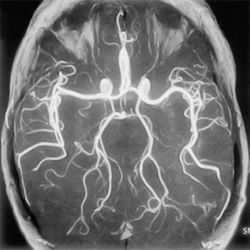

МР-ангиография

Магнитно-резонансная ангиография (МРА) — метод получения изображения просвета сосудов при помощи магнитно-резонансного томографа. Метод позволяет оценивать как анатомические, так и функциональные особенности кровотока. МРА основана на отличии сигнала от перемещающихся протонов (крови) от окружающих неподвижных тканей, что позволяет получать изображения сосудов без использования каких-либо контрастных средств — бесконтрастная ангиография (фазово-контрастная МРА и время-пролётная МРА). Для получения более чёткого изображения применяются особые контрастные вещества на основе парамагнетиков (гадолиний).